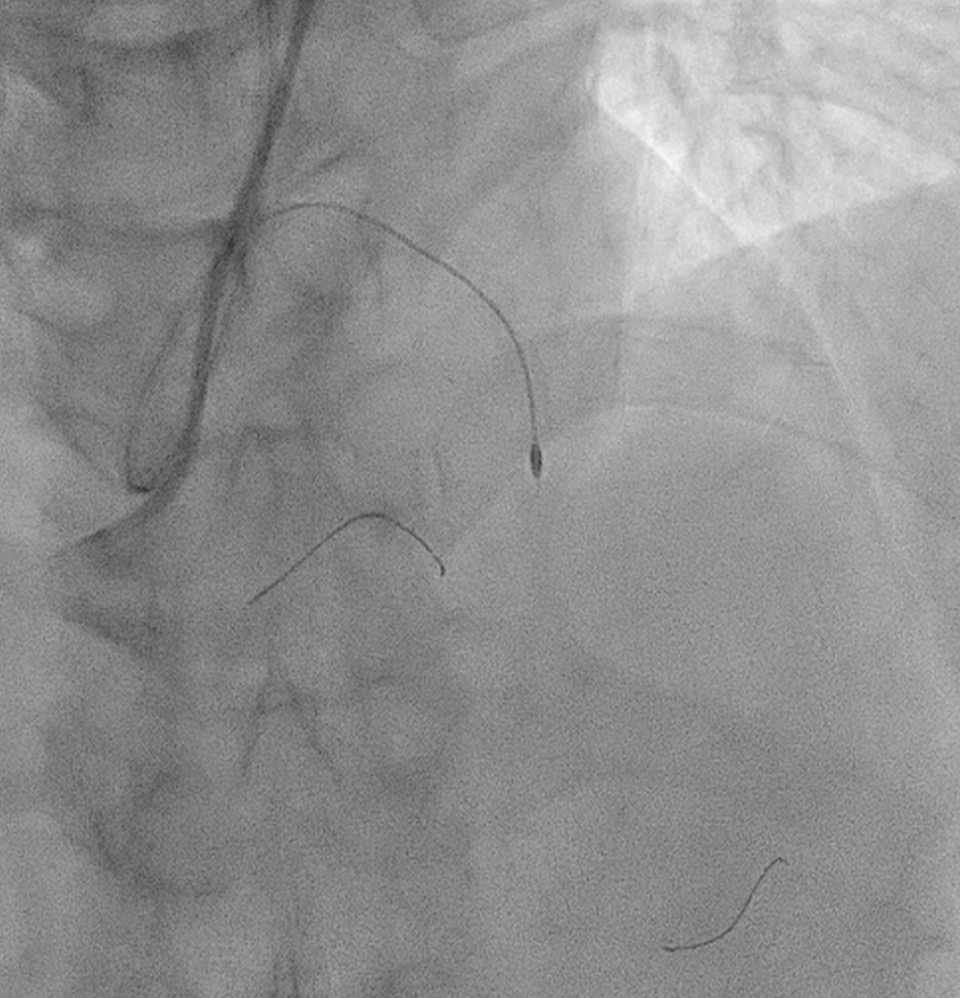

WE DECIDED TO INTERVENE THE CTO MLAD IN VIEW PERSISTENT ANGINA. BILATERAL RADIAL ARTERY PUNCTURE, WITH ANTEGRADE APPROACH. WE ENGAGED RIGHT CORONARY ARTERY WITH JR4 6 FR AND WIRED DOWN WITH RUNTHROUGH FLOPPY. ENGAGED THE LEFT CORONARY ARTERY WITH EBU 3.5 7FR. INITIALLY TRIED TO WIRE THE LAD WITH FINECROSS MICROCATHER (MC) USING SION BLACK WIRE BUT FAILED. SUBSEQUENTLY CHANGED TO GAIA 1ST AND MANAGED TO CROSS SUCCESSFULLY. IVUS SHOWED 360 DEGREE CALCIFICATION WITH 270 DEGREE CALCIFICATION MORE THAN 5 MM, IVUS CALCIUM SCORE 2. CALCIUM DEBULKING WAS DONE USING ROTABLATION WITH 1.5 BURR RUN 3 TIMES AT 220 KRPM FOR 10 SECS AND POLISHING RUN TWICE AT 140 KRPM. POST ROTA SHOWED PRESENCE OF FRACTURED CALCIUM WITH REVEBERATION SIGN. LESIONS WAS PREPARED FURTHER USING WOLVERINE 3.0 X 10MM AND 3.5 X 10MM. POST CUTTING BALLOON SHOT SHOWED NO DISSECTION, TIMI 3 FLOW AND RESIDUAL STENOSIS 30%. DECIDED FOR DCB WITH PANTERA LUX 3.0 X 20MM AND AGENT 3.50 X 30MM. FINAL SHOT SHOWED TIMI3 FLOW, NO DISSECTION SEEN. PATIENT REMAIN ASYMPTOMATIC AT 6 MONTHS AND REPEATED COROS SHOWED MODERATE STENOSIS AT MLAD WITH NEGATIVE FFR (0.92).

Case Summary